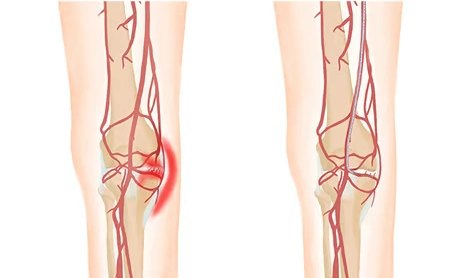

Genicular Artery Embolization (GAE) is a minimally invasive, image-guided treatment used to relieve chronic knee pain caused by knee osteoarthritis. In osteoarthritis, abnormal inflammation and increased blood flow around the knee joint contribute to pain and swelling. GAE works by selectively reducing this abnormal blood supply, helping to decrease inflammation and pain.

Genicular artery embolization is performed through a small puncture in the groin or foot without any surgical incision. Using real-time imaging guidance, a thin catheter is navigated to the small arteries supplying the inflamed areas around the knee. Tiny embolic particles are then delivered to reduce abnormal blood flow and inflammation.

GAE works by reducing abnormal blood flow to inflamed areas around the knee, which helps decrease inflammation and pain.